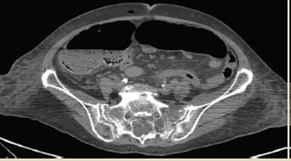

En la TAC de abdomen en corte axial se apreció dilatación importante de asas de colon, con diámetro transverso máximo de 15 cm, niveles hidroaéreos y neumatosis intestinal (figura 11). Con base en el cuadro clínico-radiológico e inestabilidad hemodinámica, se decidió realizar tiempo quirúrgico de urgencia, identificando colon sigmoides rotado en sentido antihorario, de 60 cm de longitud por 15 cm en su diámetro mayor, mesenterio redundante de colon descendente y sigmoides, aspecto necrótico con múltiples adherencias y segmentos de colon adyacente de apariencia violácea con parches de isquemia transmural (figura 12). Al no identificar peristaltismo reflejo al estimulo táctil ni recuperación de coloración tras destorsión y estímulo térmico, se determinó segmento intestinal no viable (figura 13). Se realizó procedimiento de Hartmann.

Figura 11 TAC simple de abdomen, corte axial; dilatación importante de asas de colon, con diámetro transverso máximo de 15 cm, niveles hidroaéreos y neumatosis intestinal